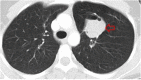

Hydatid cyst caused by the larval form of Echinococcus is a worldwide zoonosis. The lungs and liver are the most common sites involved. While the lung parenchyma is the most common site within the thorax, it may develop in any extrapulmonary region including the pleural cavity, fissures, mediastinum, heart, vascular structures, chest wall, and diaphragm. Imaging plays a pivotal role not only in the diagnosis of hydatid cyst, but also in the visualization of the extent of involvement and complications. The aim of this pictorial review was to comprehensively describe the imaging findings of thoracic hydatid cyst including pulmonary and very unusual extrapulmonary involvements. An outline is also given for the findings of complications and differential diagnosis of thoracic hydatid cyst.